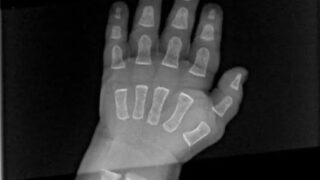

赤ちゃんのレントゲン写真がマジで衝撃的すぎワロタ

これは、赤ちゃんの手にX線検査を行った画像です。View Redditどんな話題?驚愕!赤ちゃんの骨は「浮いている」!?レントゲン写真で見る赤ちゃんの骨は、大人のようにカチッと固まっておらず、まるで軟骨のように見える部分が多いんです。これは...